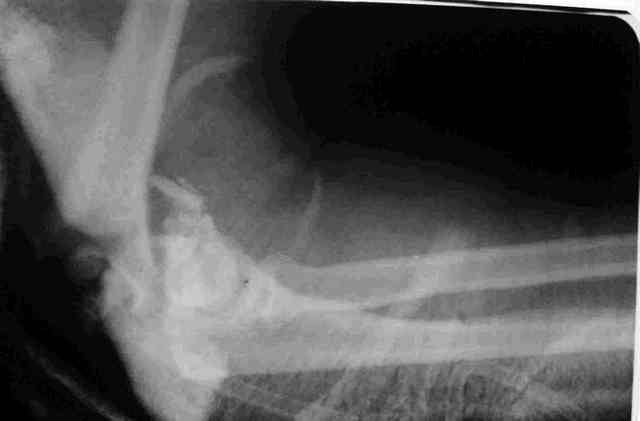

Прошу оказать помощь в определении дальнейшей тактики лечения открытого оскольчатого

перелома дистального отдела плеча, осложненного гнойной инфекцией у пациентки с

сочетанной травмой.

Пациентка получила сочетанную травму в результате падения с высоты. В числе прочих

повреждений открытый оскольчатый перелом дистального отдела плечевой кости. Выполнено

ПХО, гипсовая иммобилизация. На следующие сутки клиника гнойной инфекции. Произведена

вторичная гнойная хирургическая обработка раны, стабилизация перелома аппаратом,

вакуумное дренирование. В настоящий момент гнойного отделяемого нет. (отделяется

синовиальная жидкость. Наложены вторичные швы. Вопрос - какова дальнейшая тактика в случае

заживления раны ( открытый остеосинтез или функциональное лечение). Что делать в случает

возобновления гнойного процесса.